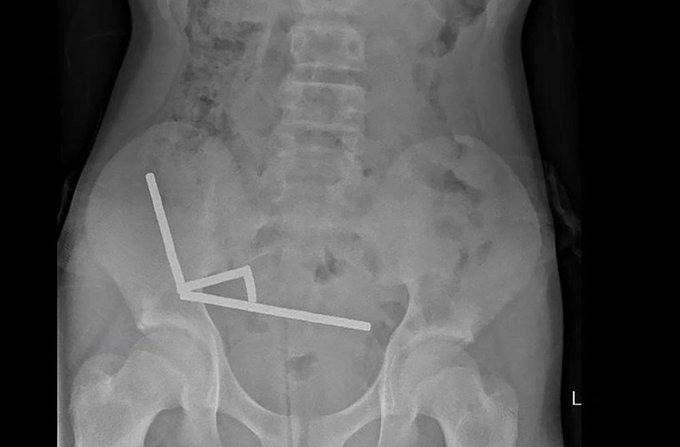

Các bác sĩ đã lấy ra tới 100 viên nam châm từ ruột của một cậu bé 13 tuổi.

Các bác sĩ phẫu thuật tại Bệnh viện Tauranga đã viết trên Tạp chí Y khoa New Zealand rằng cậu bé tuổi teen đã nuốt khoảng 80 đến 100 viên nam châm nhỏ một tuần trước ca phẫu thuật. Cậu bé đã mua chúng ở Temu.

Cậu bé tiết lộ đã nuốt khoảng 80–100 80–100 nam châm (neodymium) loại mạnh, kích thước 5x2mm khoảng một tuần trước đó, được mua từ một chợ trực tuyến ở nước ngoài (Temu)".